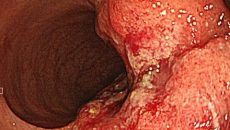

胃内視鏡検査でわかる疾患

⼤腸内視鏡検査でわかる疾患